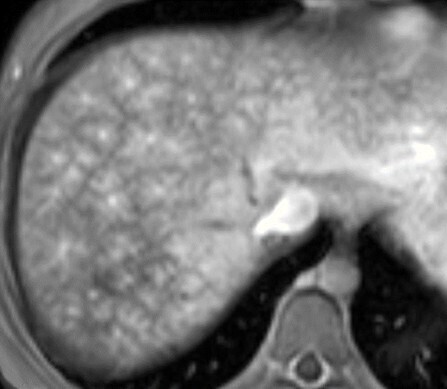

Perfusion en mosaïque

Le rehaussement (ou perfusion) en mosaïque du foie est très évocateur d’une maladie vasculaire. Il correspond à un rehaussement hétérogène (dit en feuille de fougère), surtout visible en périphérie et dans le foie droit, en particulier aux temps précoces (artériel et portal), puis qui s’homogénéise au temps tardif (fig. 3). Cet aspect est pathognomonique d’une dilatation sinusoïdale. Il doit donc faire rechercher toute cause de perturbation du retour veineux hépatique (thrombose des veines hépatiques, cardiopathie surtout droite, etc.).